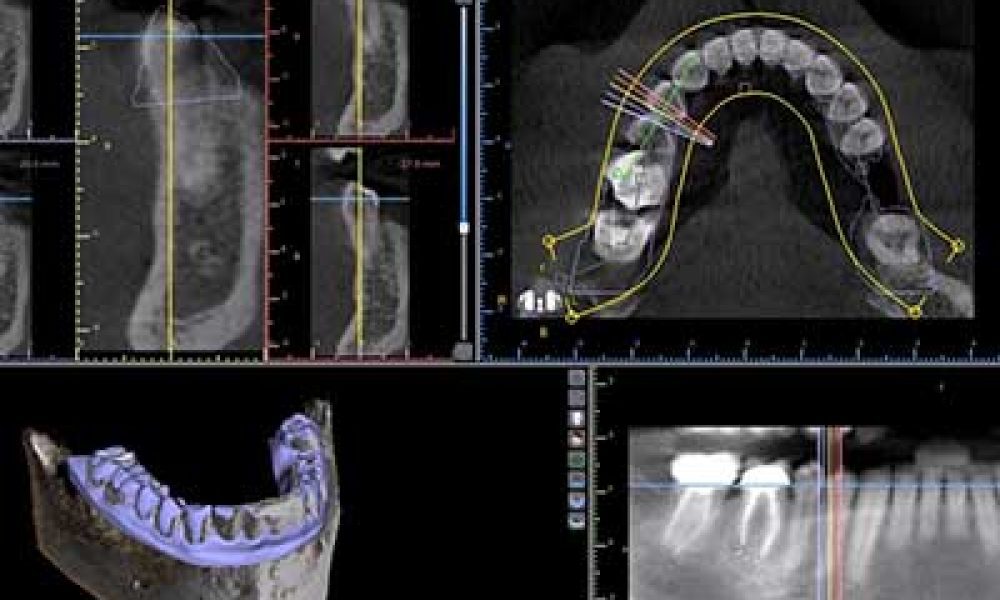

Dental implants are the state-of-the art approach to replacing missing teeth. Whether you are missing a single tooth or nearly all of your teeth, dental…

When a person loses a tooth, the best way to replace it is with a dental implant. In some cases, due to insufficient or deficient bone in the jaw, a dental…